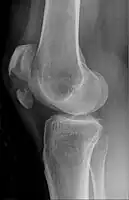

Transverse fracture of patella

Comminuted fracture of patella

Osteochondral fracture of patella

Vertical patella fracture